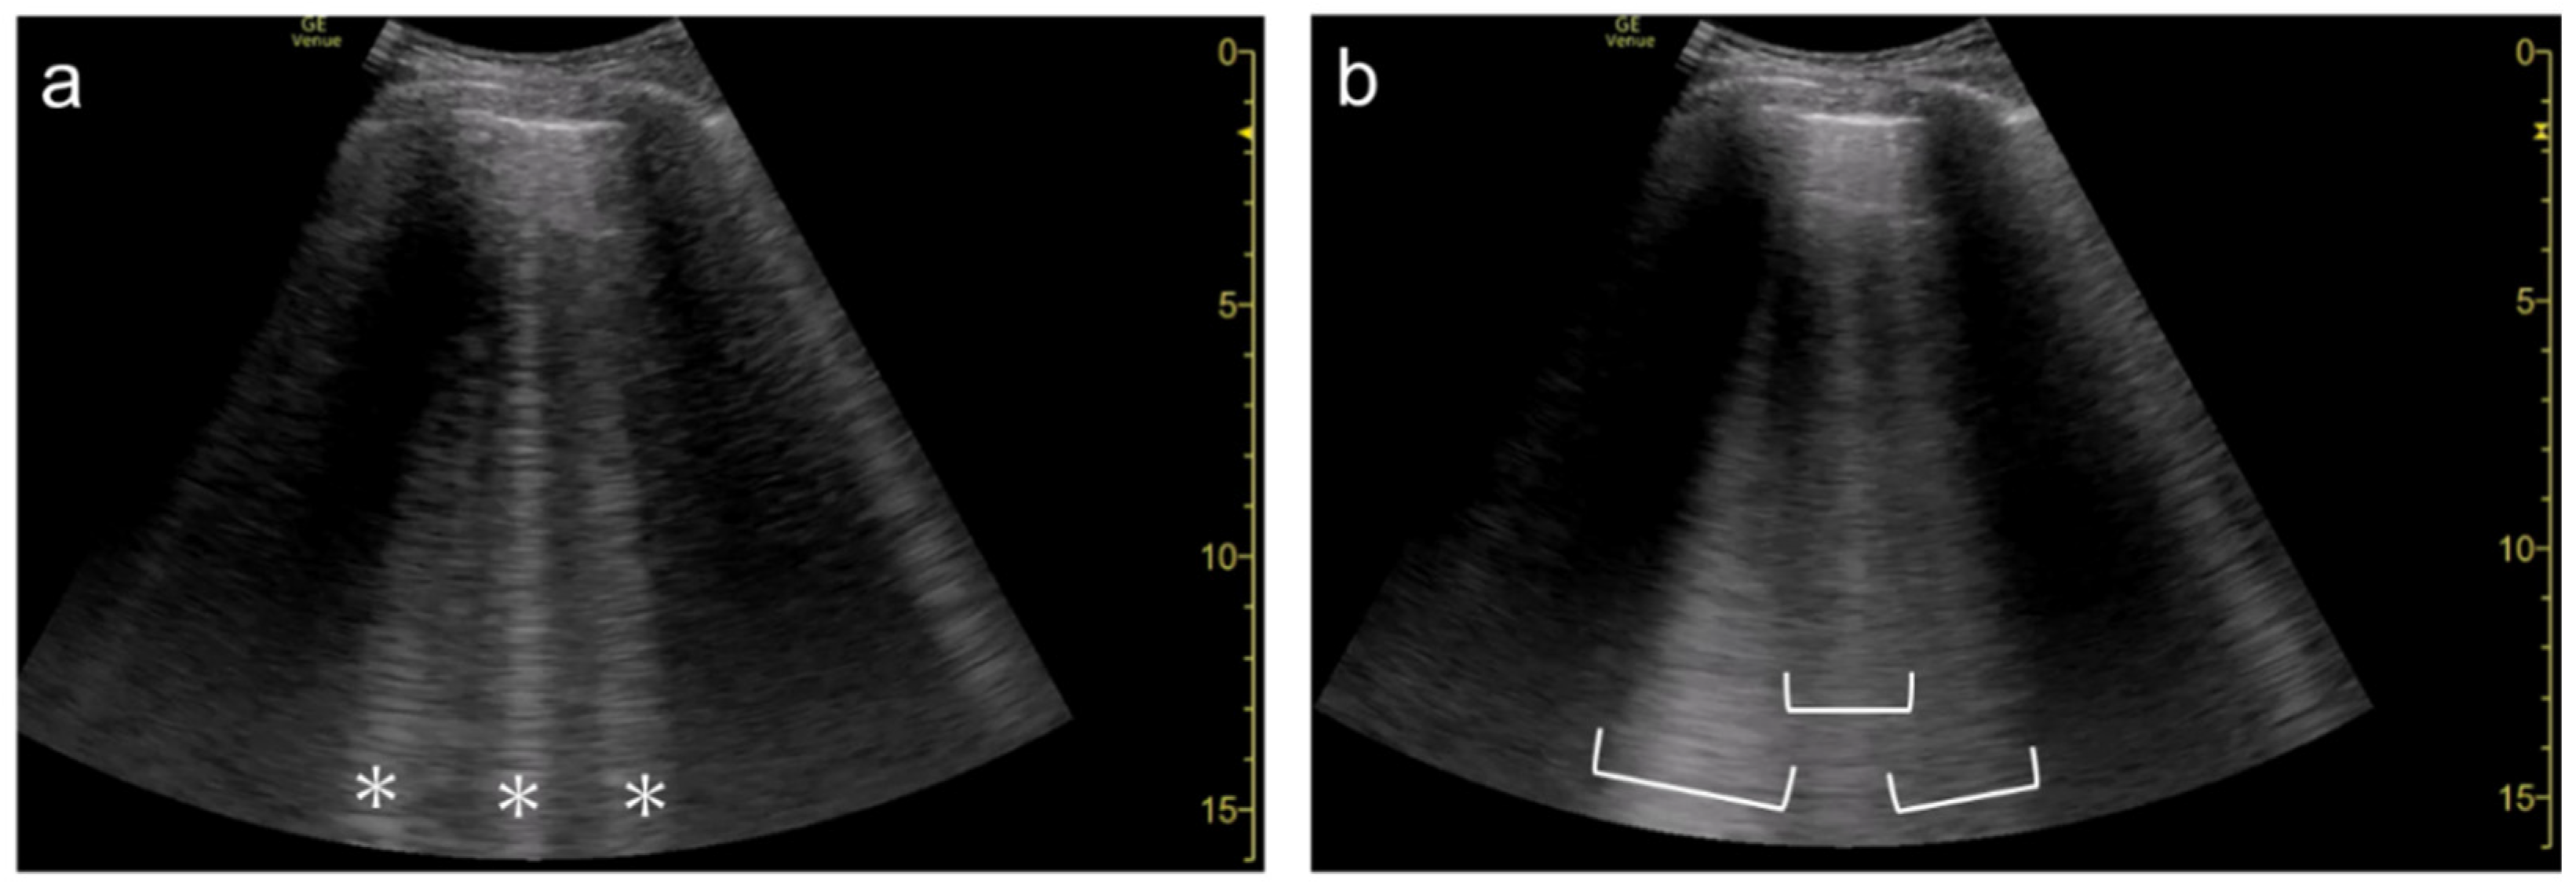

3.1. Spatial Compound Imaging